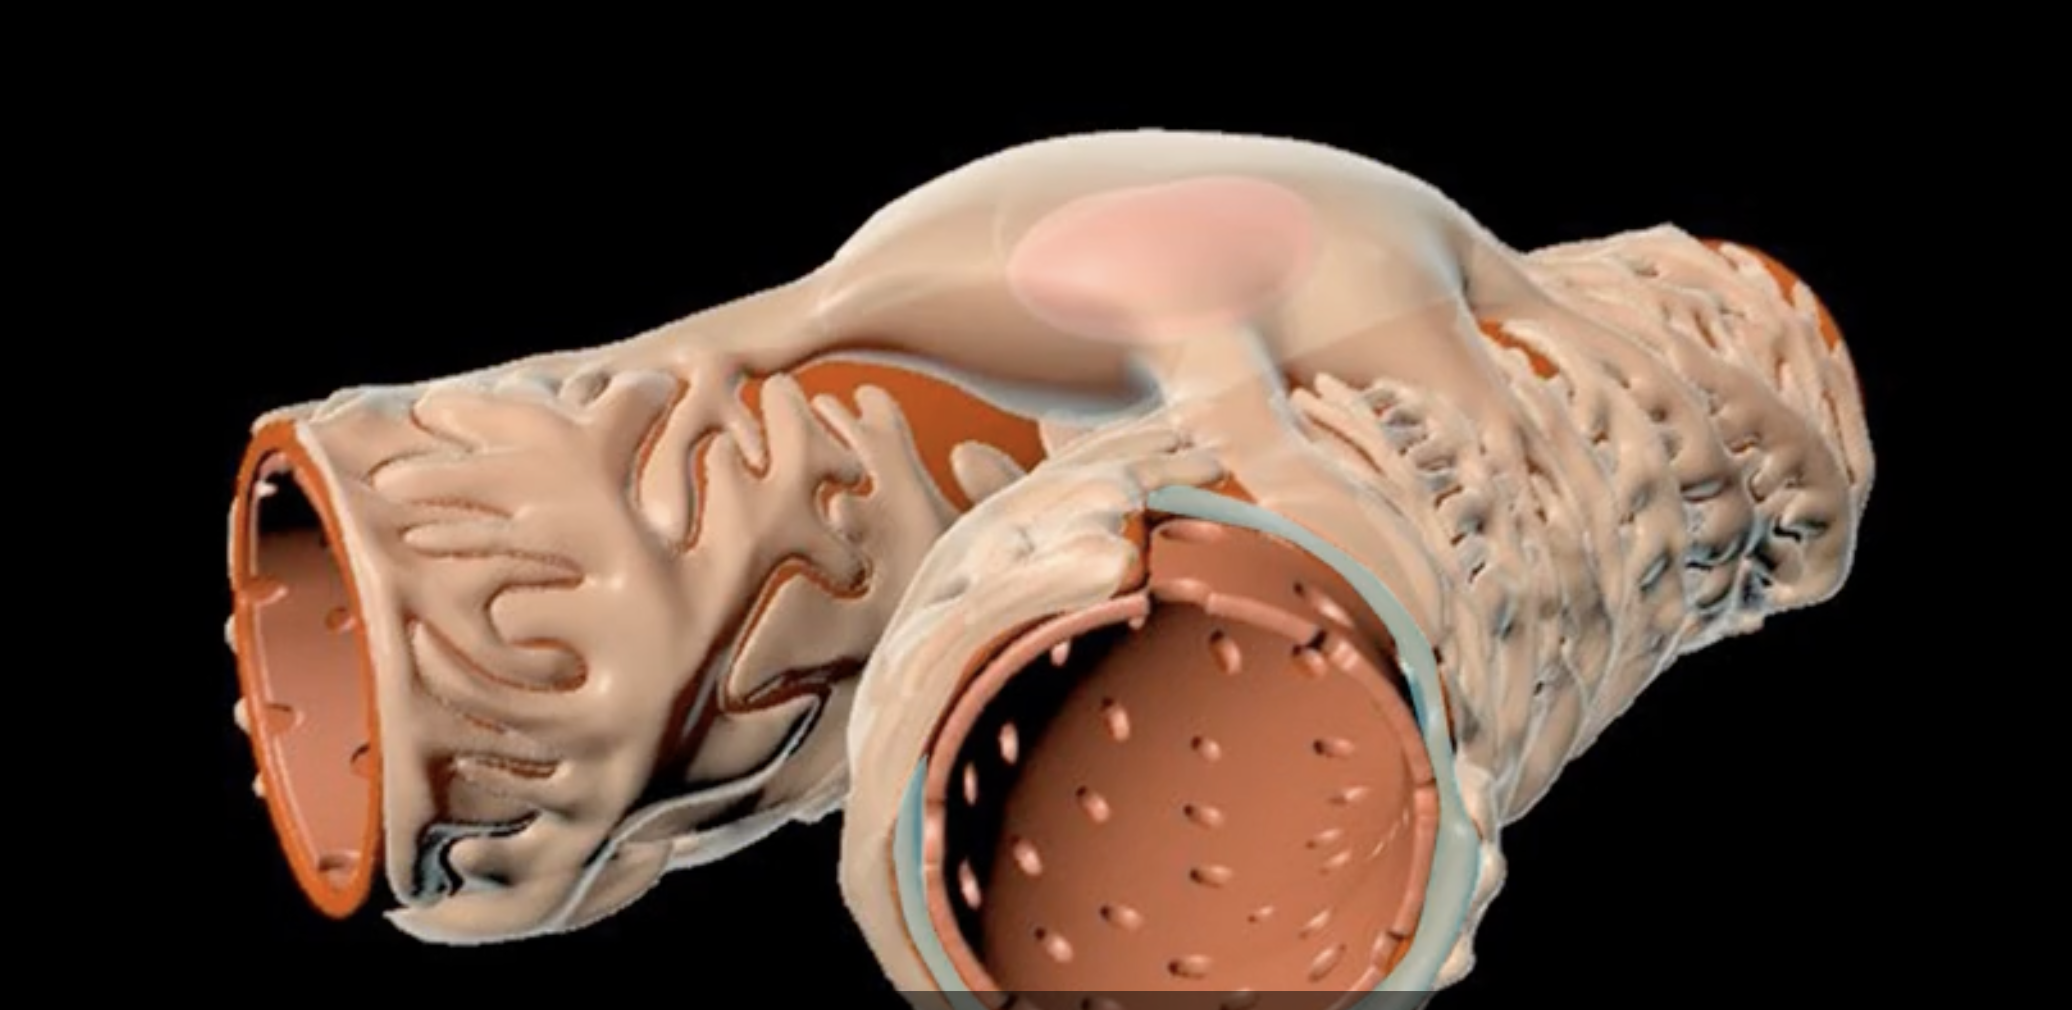

green: fibrous renal capsule

blue: perirenal fat

green and blue surrounding each kidney

orange: renal fascia

purple: pararenal fat

orange and purple

renal cortex

green

renal medulla

blue

renal columns

yellow

renal pyramids

purple

renal lobe

orange

renal papilla

minor calyx

teal

major calyces

renal pelvis

minor and major calyces